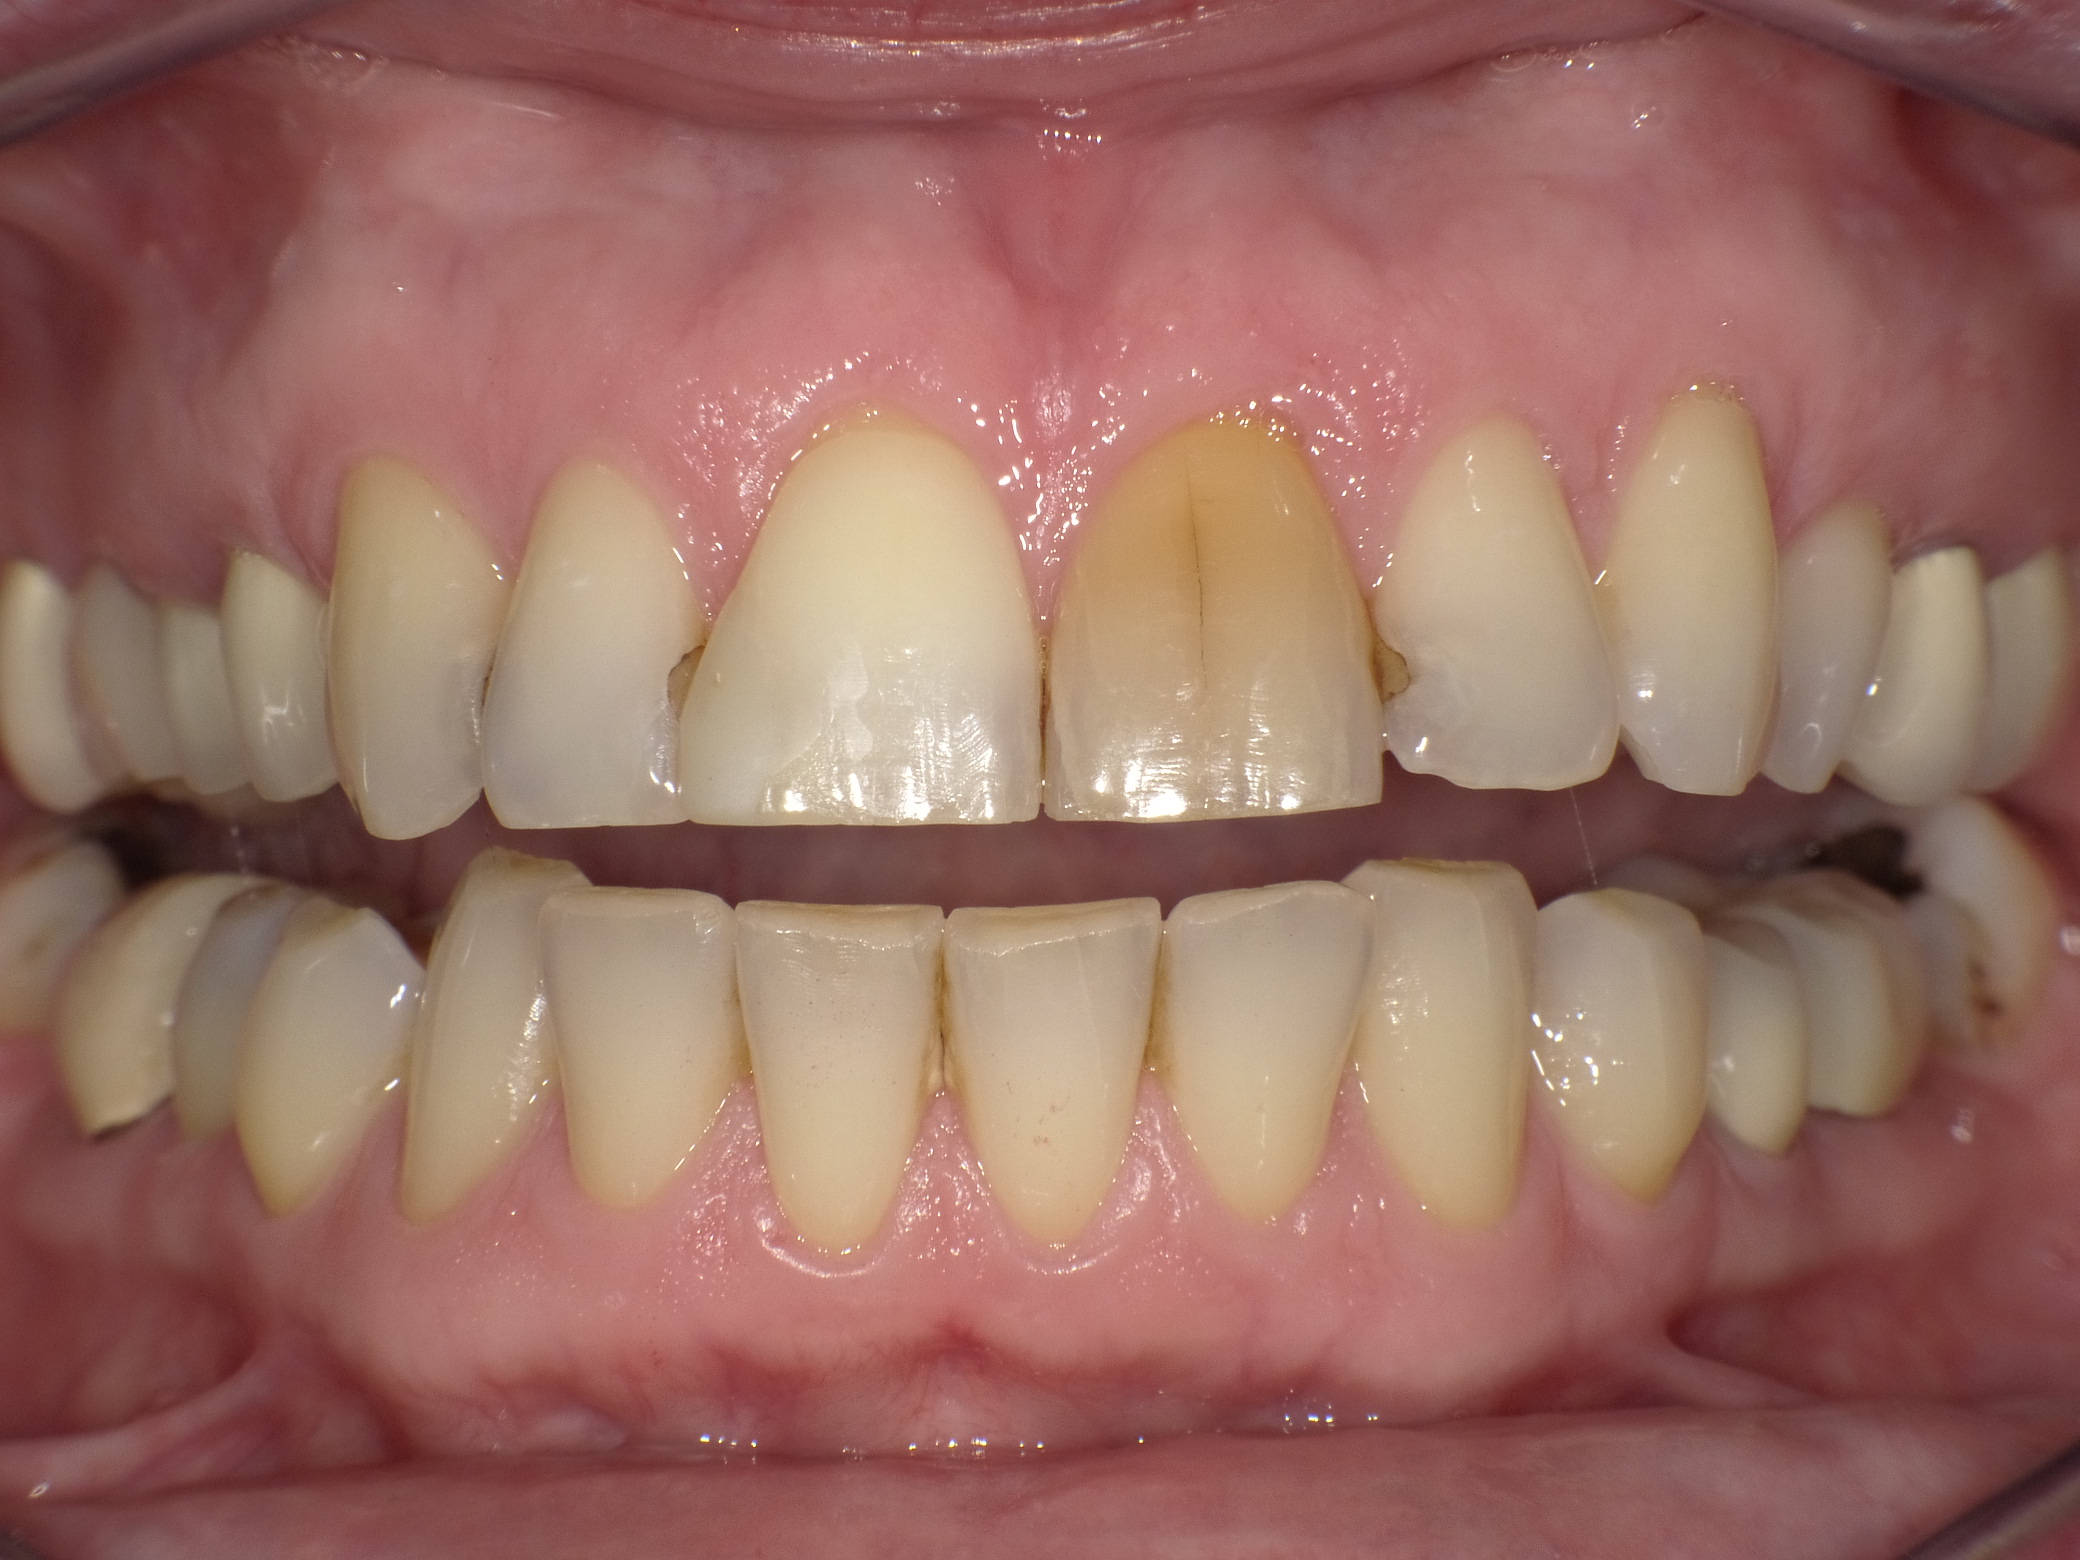

Diverse Vorbehandlungen mit für die Patientin absolut inakzeptablem Ergebnis

Vorher: Diverse Vorbehandlungen mit für die Patientin absolut inakzeptablem Ergebnis

Komplette Veränderung mit vollkeramischen Kronen und Veneers in nur 2 Langzeitterminen; auch hier nachher ganz anderes Auftreten der Patientin, die ihre Zähne jetzt gerne zeigt und wieder gerne lacht

Nachher: Komplette Veränderung mit vollkeramischen Kronen und Veneers in nur 2 Langzeitterminen; auch hier nachher ganz anderes Auftreten der Patientin, die ihre Zähne jetzt gerne zeigt und wieder gerne lacht